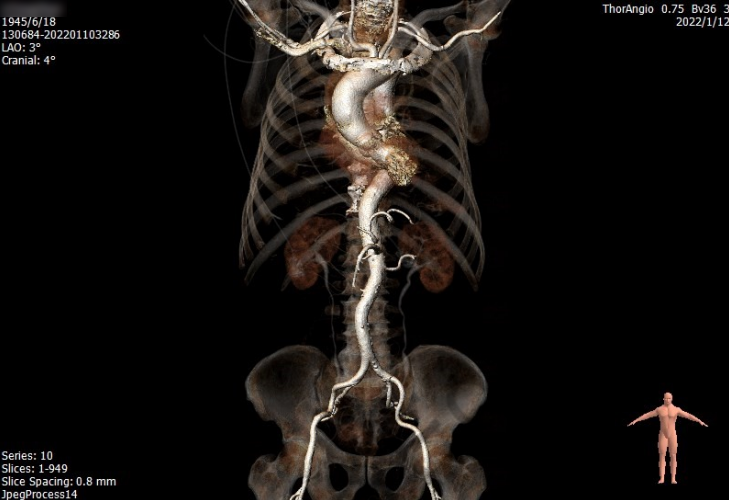

主动脉CT

瓣环周长:71.7mm

平均直径:23.0mm

LVOT周长:73.0mm

平均直径:23.2mm

主动脉窦部钙化分布

主动脉弓部大折角

入路迂曲

1. 患者为 TypeI型二叶瓣 ,瓣叶增厚,中度钙化。钙化分布不均匀,主要分布瓣叶交界。左冠高度低,瓣叶长,窦宽相对瓣膜可。右冠高度可,瓣叶长,冠脉开口附近在钙化,窦宽相对瓣膜可。

2.主动脉弓迂曲,折角较大,可能会影响瓣膜通过及轴向。